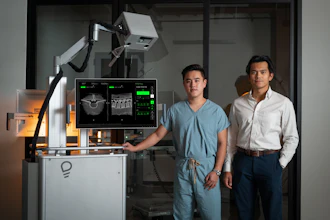

People who received gentle electric currents on the back of their heads learned to maneuver a robotic surgery tool in virtual reality and then in a real setting much more easily than people who didn’t receive those nudges, a new study shows.

The findings offer the first glimpse of how stimulating a specific part of the brain called the cerebellum could help health care professionals take what they learn in virtual reality to real operating rooms, a much-needed transition in a field that increasingly relies on digital simulation training, said author and Johns Hopkins University roboticist Jeremy D. Brown.

Participants drove a surgical needle through three small holes, first in a virtual simulation and then in a real scenario using the da Vinci Research Kit, an open-source research robot. The exercises mimicked moves needed during surgical procedures on organs in the belly, the researchers said.

Noninvasive brain stimulation is a way to influence certain parts of the brain from outside the body, and scientists have shown how it can benefit motor learning in rehabilitation therapy, the researchers said. With their work, the team is taking the research to a new level by testing how stimulating the brain can help surgeons gain skills they might need in real-world situations, said co-author Gabriela Cantarero, a former assistant professor of physical medicine and rehabilitation at Johns Hopkins.

Robotic surgery systems provide significant benefits for clinicians by enhancing human skill. They can help surgeons minimize hand tremors and perform fine and precise tasks with enhanced vision.